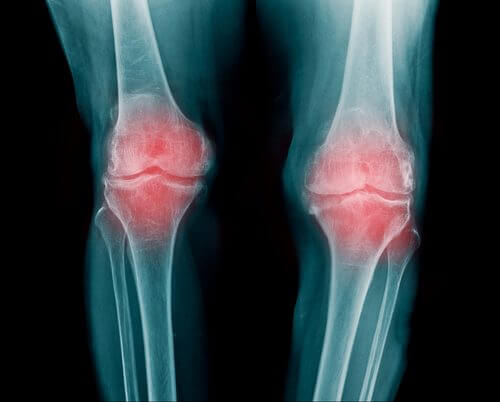

Les articulations se situent au niveau des terminaisons osseuses du corps et sont chargées de protéger les condyles. Elles jouent un rôle fondamental dans le mouvement des extrémités inférieures et supérieures.

Un usage intensif des articulations peut provoquer divers problèmes tels que l’ostéoarthrite.

Entre chaque articulation se trouve un segment de cartilage, qui empêche le frottement des os. Cependant, le passage du temps provoque des dommages progressifs, qui engendrent des douleurs et de l’inflammation.

C’est pourquoi la possibilité de mouvement se réduit considérablement, ainsi que la possibilité de réaliser différentes activités (sportives ou du quotidien).